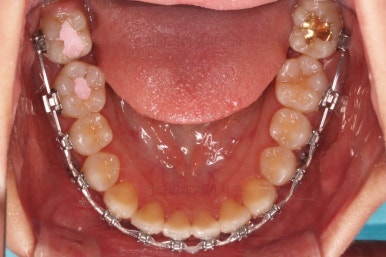

부산교정 키다리아저씨치과에 처음 내원하셨을 당시의 입안 모습과 X-ray 사진입니다.

맨 안쪽 치아가 마치 사랑니인 것처럼 누워있고 애매하게 나와있었어요.

문제는 해당 치아가 썩었다는건데 기울어 있는 치아를 제대로 치료할 방법은 사실상 없죠. 앞에 치아에 가려진 부분이 썩었으니깐요.

초진 시의 다른 부위들 사진입니다.

약간의 주걱턱 느낌에 약간의 돌출감, 전반적인 치열의 가지런한 느낌은 나쁘진 않았지만 약간의 불량한 교합상태였어요.